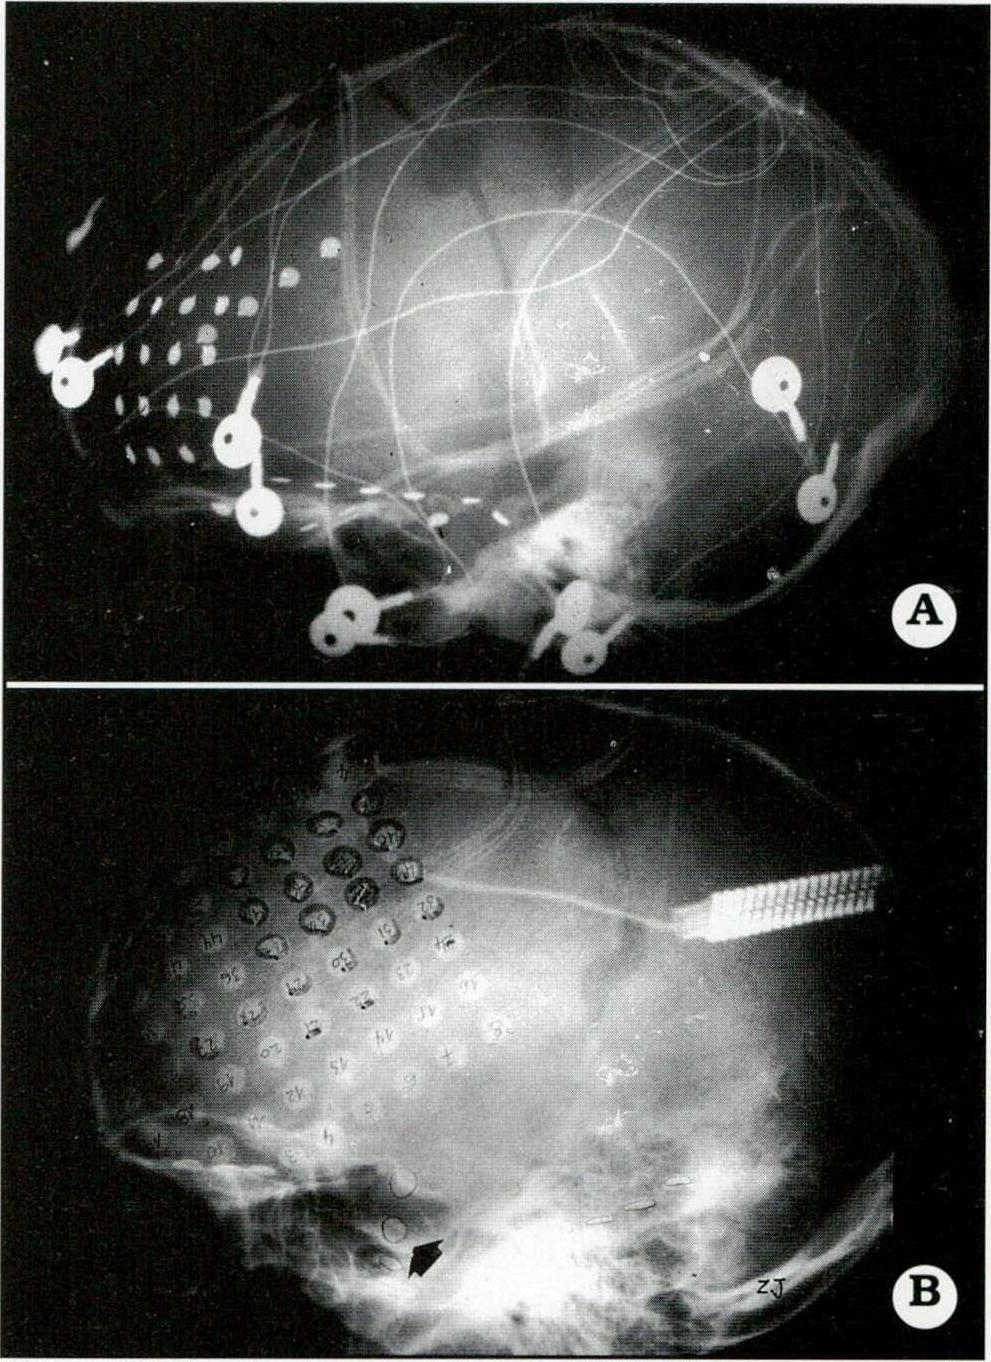

En 11/60 pacientes estudiados con videotelemetría fue necesario recurrir a la utilización de electrodos intracraneanos9. Esto implicó efectuar cirugías en dos tiempos: uno inicial para la colocación de los electrodos y el traslado del paciente a la unidad de Video-telemetría; luego de captar un número suficiente de crisis, no menos de 3 a 5, se realizó segundo tiempo quirúrgico acorde a la estrategia definida previamente. (Figs. 3 y 4).

Fig. 3. A. Paciente de 9 años de edad con crisis frontales. Se implantaron una plaqueta con 20 electrodos cubriendo el lóbulo frontal izquierdo y 2 tiras, de 4 electrodos cada una, subtemporal polar y mesial. Se definió así el origen frontal de la epilepsia. B. Paciente de 11 años de edad con una extensa atrofia parietotemporal. Se implantó una plaqueta de 64 electrodos cubriendo ampliamente el lóbulo frontal y 1 tira de 4 electrodos subtemporal (flecha). En la unidad de videotelemetría no sólo se registraron crisis que ubicaron la ZEP (marcados con círculos y semicírculos), sino que también mediante estimulación cortical y PESS del nervio mediano se localizó el área motora primaria de la mano (electrodos sombreados). Esto determinó el límite posterior de la corticectomía efectuada.